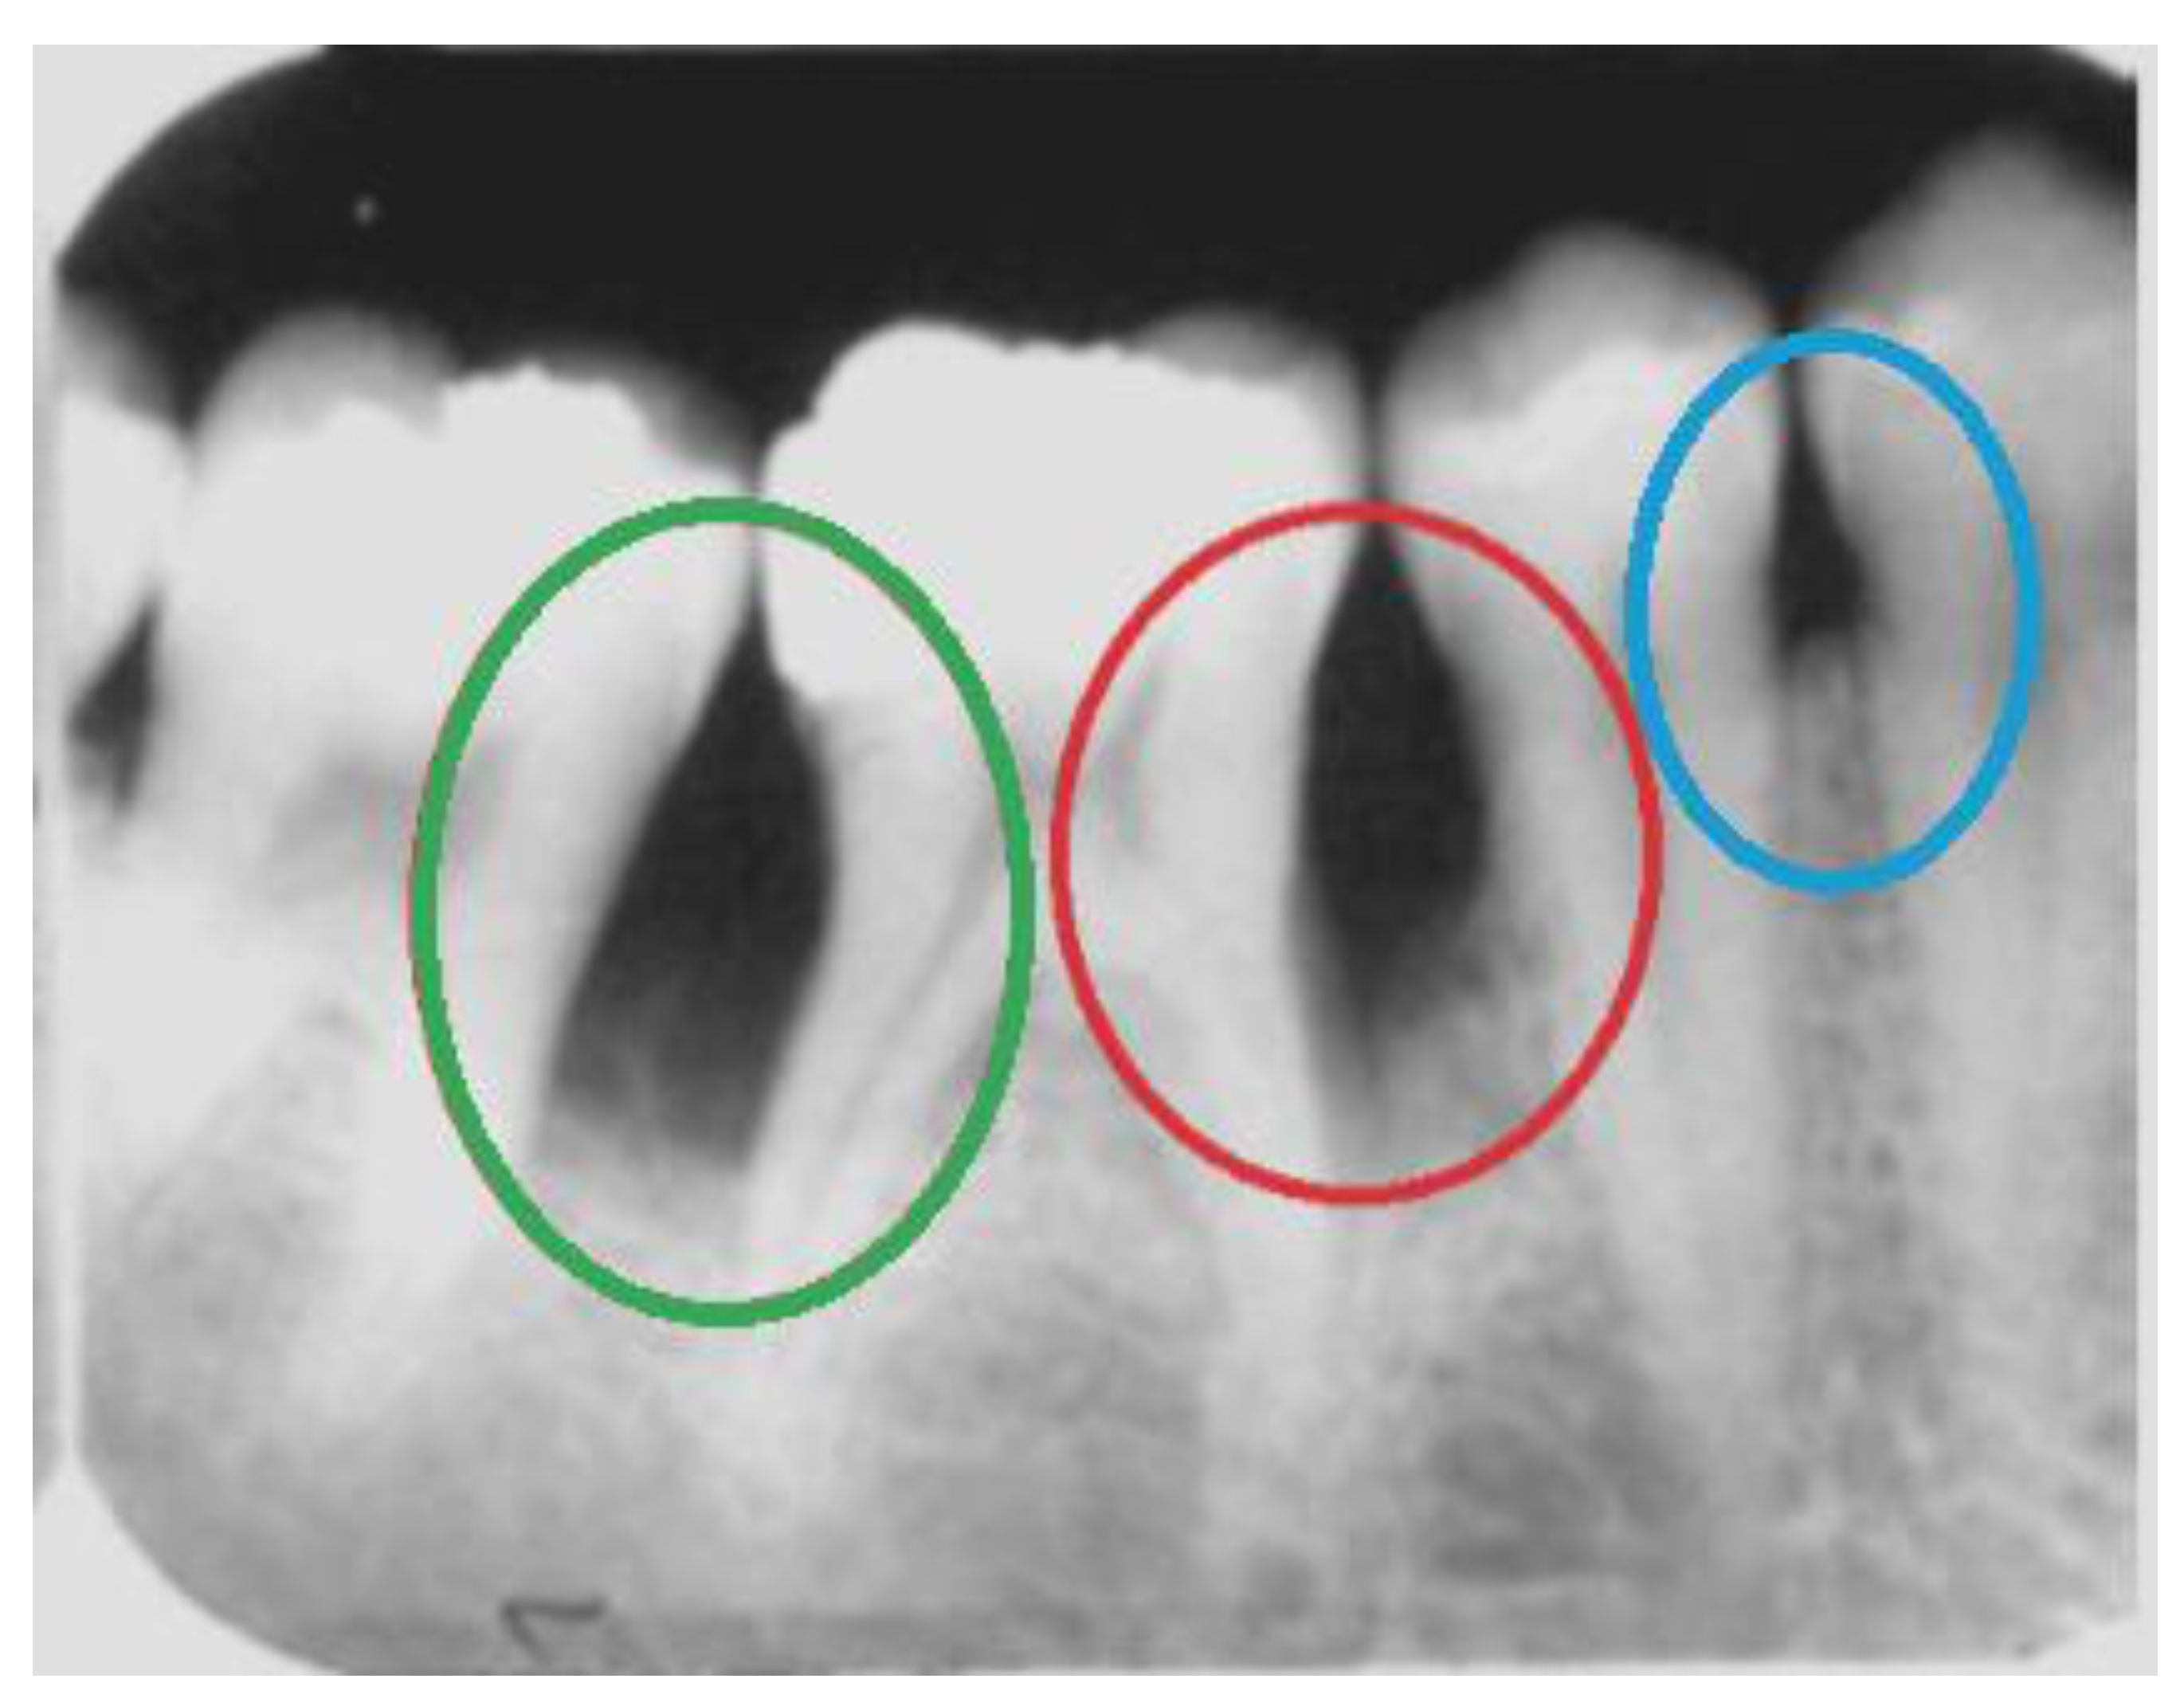

In this work, we focus on horizontal bone loss, vertical bone defects, and interdental craters. These patterns of bone loss may be visible radiographically. In general, interproximal bone loss can be radiographically and clinically observed as an increase in the distance from the enamel–cement junction to the alveolar crest. Horizontal bone loss consists of a horizontal loss in the alveolar bone’s height; i.e., the tissue destruction is symmetrical. Radiographically, vertical bone loss can be identified as a deformity in the alveolus extending apically along the root of the affected tooth from the alveolar crest. When it happens in an interproximal region between two teeth, it can be seen as an uneven lesion, more accentuated on one side. The interproximal crater consists of a lesion that radiographically can be observed as a two-walled, trough-like depression. This loss has a band-like or irregular appearance in the interdental region between adjacent teeth [28]. Figure 1 shows examples of these three types of bone loss.

Figure 1.

Examples of bone loss in a real periapical radiograph: an interproximal crater in green, vertical bone loss in red, and a horizontal bone defect in blue.